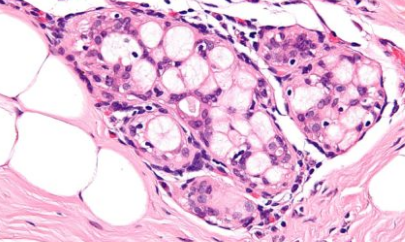

人工智能在诊断医学方面具有巨大的潜力。它可以非常快速地处理大量数据,注意到人眼无法察觉的细节。现在,赫尔辛基大学的科学家们已经证明了使用人工智能来预测靶向乳腺癌治疗效果的可能性。人工智能可用于发现肿瘤样本中的隐藏模式。

人工智能已经被用于诊断癌症并跟踪其进展。现在,科学家们开发了一种工具,可以用ERBB2(促进癌细胞生长的癌蛋白)检测乳腺癌病例的典型肿瘤形态特征。这项技术的实用性非常明显——ERBB2蛋白过度表达的患者可以从针对ERBB2受体的单克隆抗体治疗中受益。正确识别它们可以导致更明智的治疗选择和更好的结果。

芬兰的科学家表明,人工智能算法可以直接从肿瘤形态学中学习预测肿瘤ERBB2状态的模式。该研究的作者之一德米特里·比奇科夫(DmitriiBychkov)解释说:“我们的结果表明,肿瘤的形态特征包含有关疾病生物学的大量信息,可以通过机器学习方法提取。这些有价值的数据可以帮助临床决策”。研究人员用来自乳腺癌患者的真实组织样本进行了测试,发现人工智能非常擅长确定哪些患者更有可能获得更有利的疾病结果。这将非常有助于做出与治疗方案相关的选择。